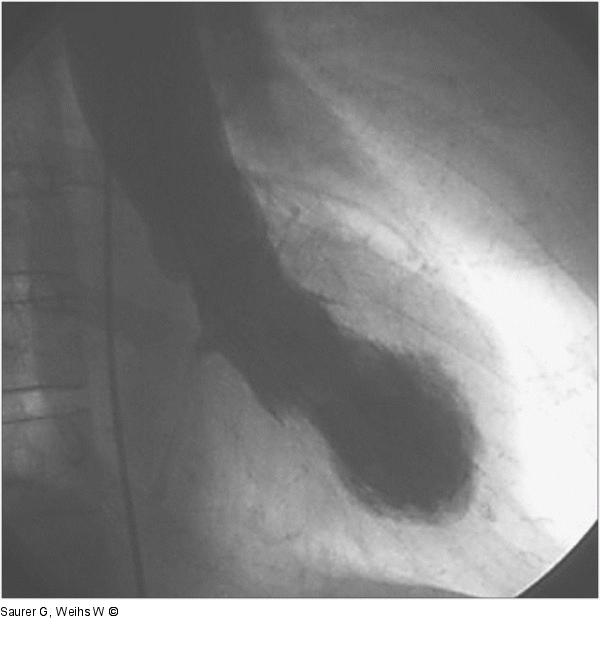

Abbildung 3b: Laevokardiogramm - Diastole - Systole Laevokardiogramm (RAO) in der Diastole (a) und Systole (b). Akinesie der apikalen Segmente ("apical ballooning") mit Hyperkontraktilität der basalen Abschnitte. |

Laevokardiogramm (RAO) in der Diastole (a) und Systole (b). Akinesie der apikalen Segmente ("apical ballooning") mit Hyperkontraktilität der basalen Abschnitte. |